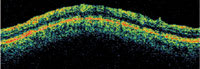

| Heidelberg slit lamp OCT of the anterior chamber angle. |

OCT of nasal and temporal sections of the anterior chamber angle including dimensions of key structures. |

Recent technological advances for glaucoma management include ocular coherence tomography (OCT) available for the anterior segment of the eye. Examples of this include Visante (Carl Zeiss Meditec) and SL OCT (Heidelberg Engineering). In addition, Portable Ophthalmic Devices is seeking FDA-approval for an ultrasonic device that is presently used for small-animal research and veterinary ophthalmic diagnosis. This device provides dynamic images of anterior segment. For instance, we can visualize changes in the configuration of the anterior chamber angle, iris, lens and ciliary body in the light and dark. This can add important information in the work-up of a glaucoma patient with a suspected narrow angle component.

The new anterior segment devices could provide high quality, dynamic, reproducible images of the anterior chamber angle without touching the eye.

The Stratus OCT (Carl Zeiss Meditec), used clinically for the evaluation of the retina, employs a 0.8 nm wavelength that cannot penetrate the sclera. As such, it is not ideal for assessing the anterior segment. However, the anterior segment version, the SL OCT, uses a longer wavelength that produces clinically useful results. Preliminary clinical studies suggest that anterior segment OCT compares favorably with conventional gonioscopy in its ability to identify potentially occludable angles.

The SL OCT allows for precise evaluation, measurement and analysis of the anterior segment, including anterior chamber depth (ACD), anterior chamber angles and the angle-to-angle distance (anterior chamber diameter). It can also assist in postoperative evaluation because it allows imaging and measurement of intraocular lenses and ocular implants.

The procedure is relatively fast. Additionally, you can perform it in complete darkness as well as in brightly lit surroundings (to assist in the dynamic assessment of the angle). The images are also digitally documented, so you can magnify, enhance, transmit and measure them. In addition, a technician can take the image, freeing the doctor to focus time on assessing the results. Compared with existing technology (ultrasound biomicroscopy), the anterior segment OCT does not contact the eye and provides a higher resolution image.